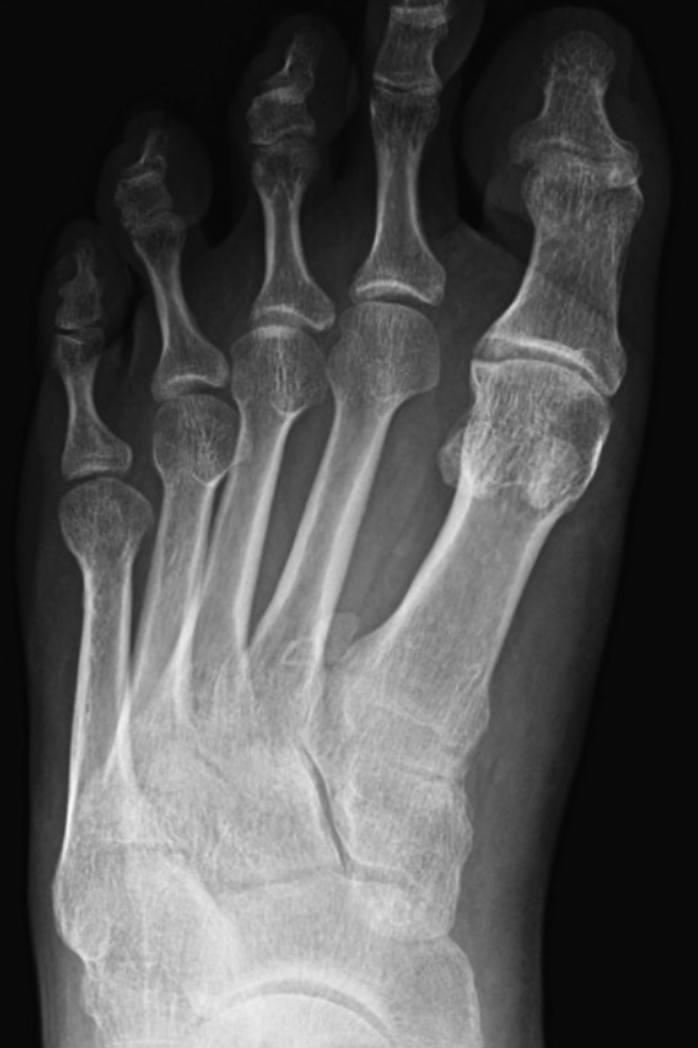

8

Q

What view is this?

A

Medial Oblique